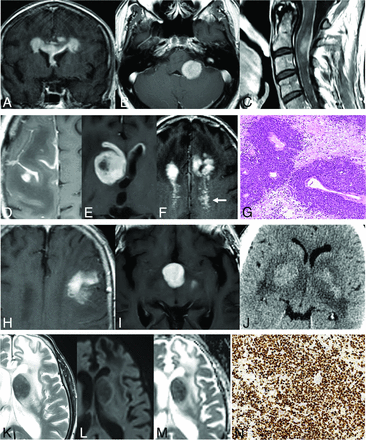

Primary DLBCLs of the CNS, EBV-positive (immunodeficiency/dysregulation-associated). Single (A) and multiple (B) lesions with prominent necrosis (C and E) and tumoral hemorrhage (D and F). Heterogeneous deep T2 hypointensity (H) of the nonenhancing central content (G) of lesions, so-called necrosis. Low-intermediate CBV on the corrected color map (I) and DSC-PWI time-intensity curve with high PSR (J), also very characteristic of this lymphoma subtype.

While conventional imaging is often insufficient to reach a presurgical diagnosis of this challenging entity, quantitative imaging, especially DSC-PWI, can provide diagnostic clues. Indeed, the perfusion features of this lymphoma follow those of low-to-intermediate CBV, high PSR, and the characteristic time-intensity curve morphology when depicting an ROI in the solid parts of tumors (Fig 4).8 Finally, the 1H-MR spectroscopy pattern seems of low value for presurgical characterization as lymphoma because this tumor has prominent mobile lipids overlapping with necrotic glioblastomas or metastasis.20

In conclusion, we suggest that in dealing with a necrohemorrhagic tumor, potential immunodeficiency/dysregulation of the patient must be thoroughly examined. If this cannot be ruled out, DLBCL EBV-positive should be considered, and careful DSC-PWI assessment can provide a presurgical diagnostic clue.